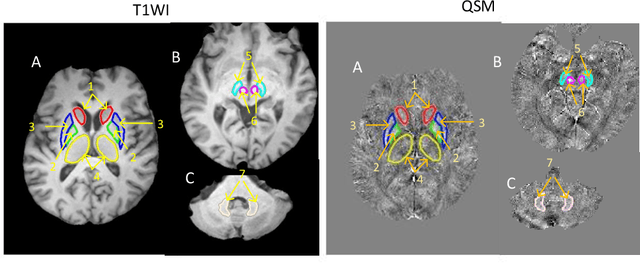

Abstract:Abnormal iron accumulation in the brain subcortical nuclei has been reported to be correlated to various neurodegenerative diseases, which can be measured through the magnetic susceptibility from the quantitative susceptibility mapping (QSM). To quantitively measure the magnetic susceptibility, the nuclei should be accurately segmented, which is a tedious task for clinicians. In this paper, we proposed a double-branch residual-structured U-Net (DB-ResUNet) based on 3D convolutional neural network (CNN) to automatically segment such brain gray matter nuclei. To better tradeoff between segmentation accuracy and the memory efficiency, the proposed DB-ResUNet fed image patches with high resolution and the patches with low resolution but larger field of view into the local and global branches, respectively. Experimental results revealed that by jointly using QSM and T$_\text{1}$ weighted imaging (T$_\text{1}$WI) as inputs, the proposed method was able to achieve better segmentation accuracy over its single-branch counterpart, as well as the conventional atlas-based method and the classical 3D-UNet structure. The susceptibility values and the volumes were also measured, which indicated that the measurements from the proposed DB-ResUNet are able to present high correlation with values from the manually annotated regions of interest.